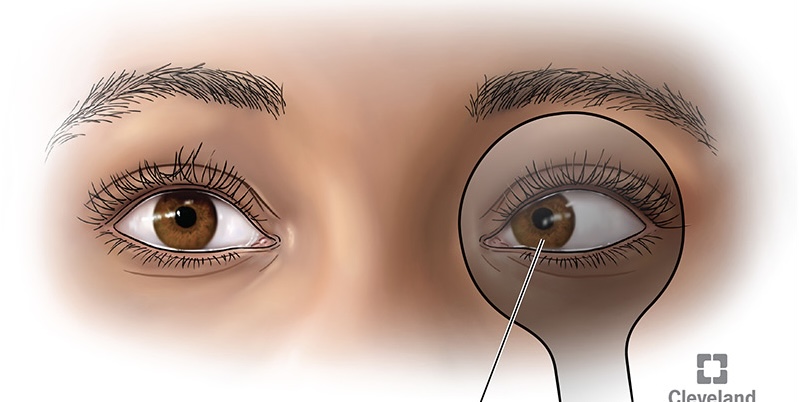

pterygium

a thickening of the bulbar conjunctiva that extends across the nasal side.